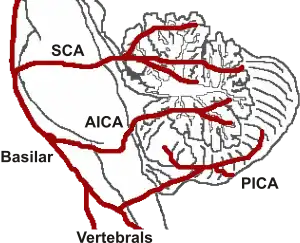

| Locked-in syndrome can be caused by a stroke at the level of the basilar artery denying blood to the pons, among other causes. | |

Unlike persistent vegetative state, in which the upper portions of the brain are damaged and the lower portions are spared, locked-in syndrome is essentially the opposite, caused by damage to specific portions of the lower brain and brainstem, with no damage to the upper brain. Injuries to the pons are the most common cause of locked-in syndrome.

- A stroke or brain hemorrhage, usually of the basilar artery